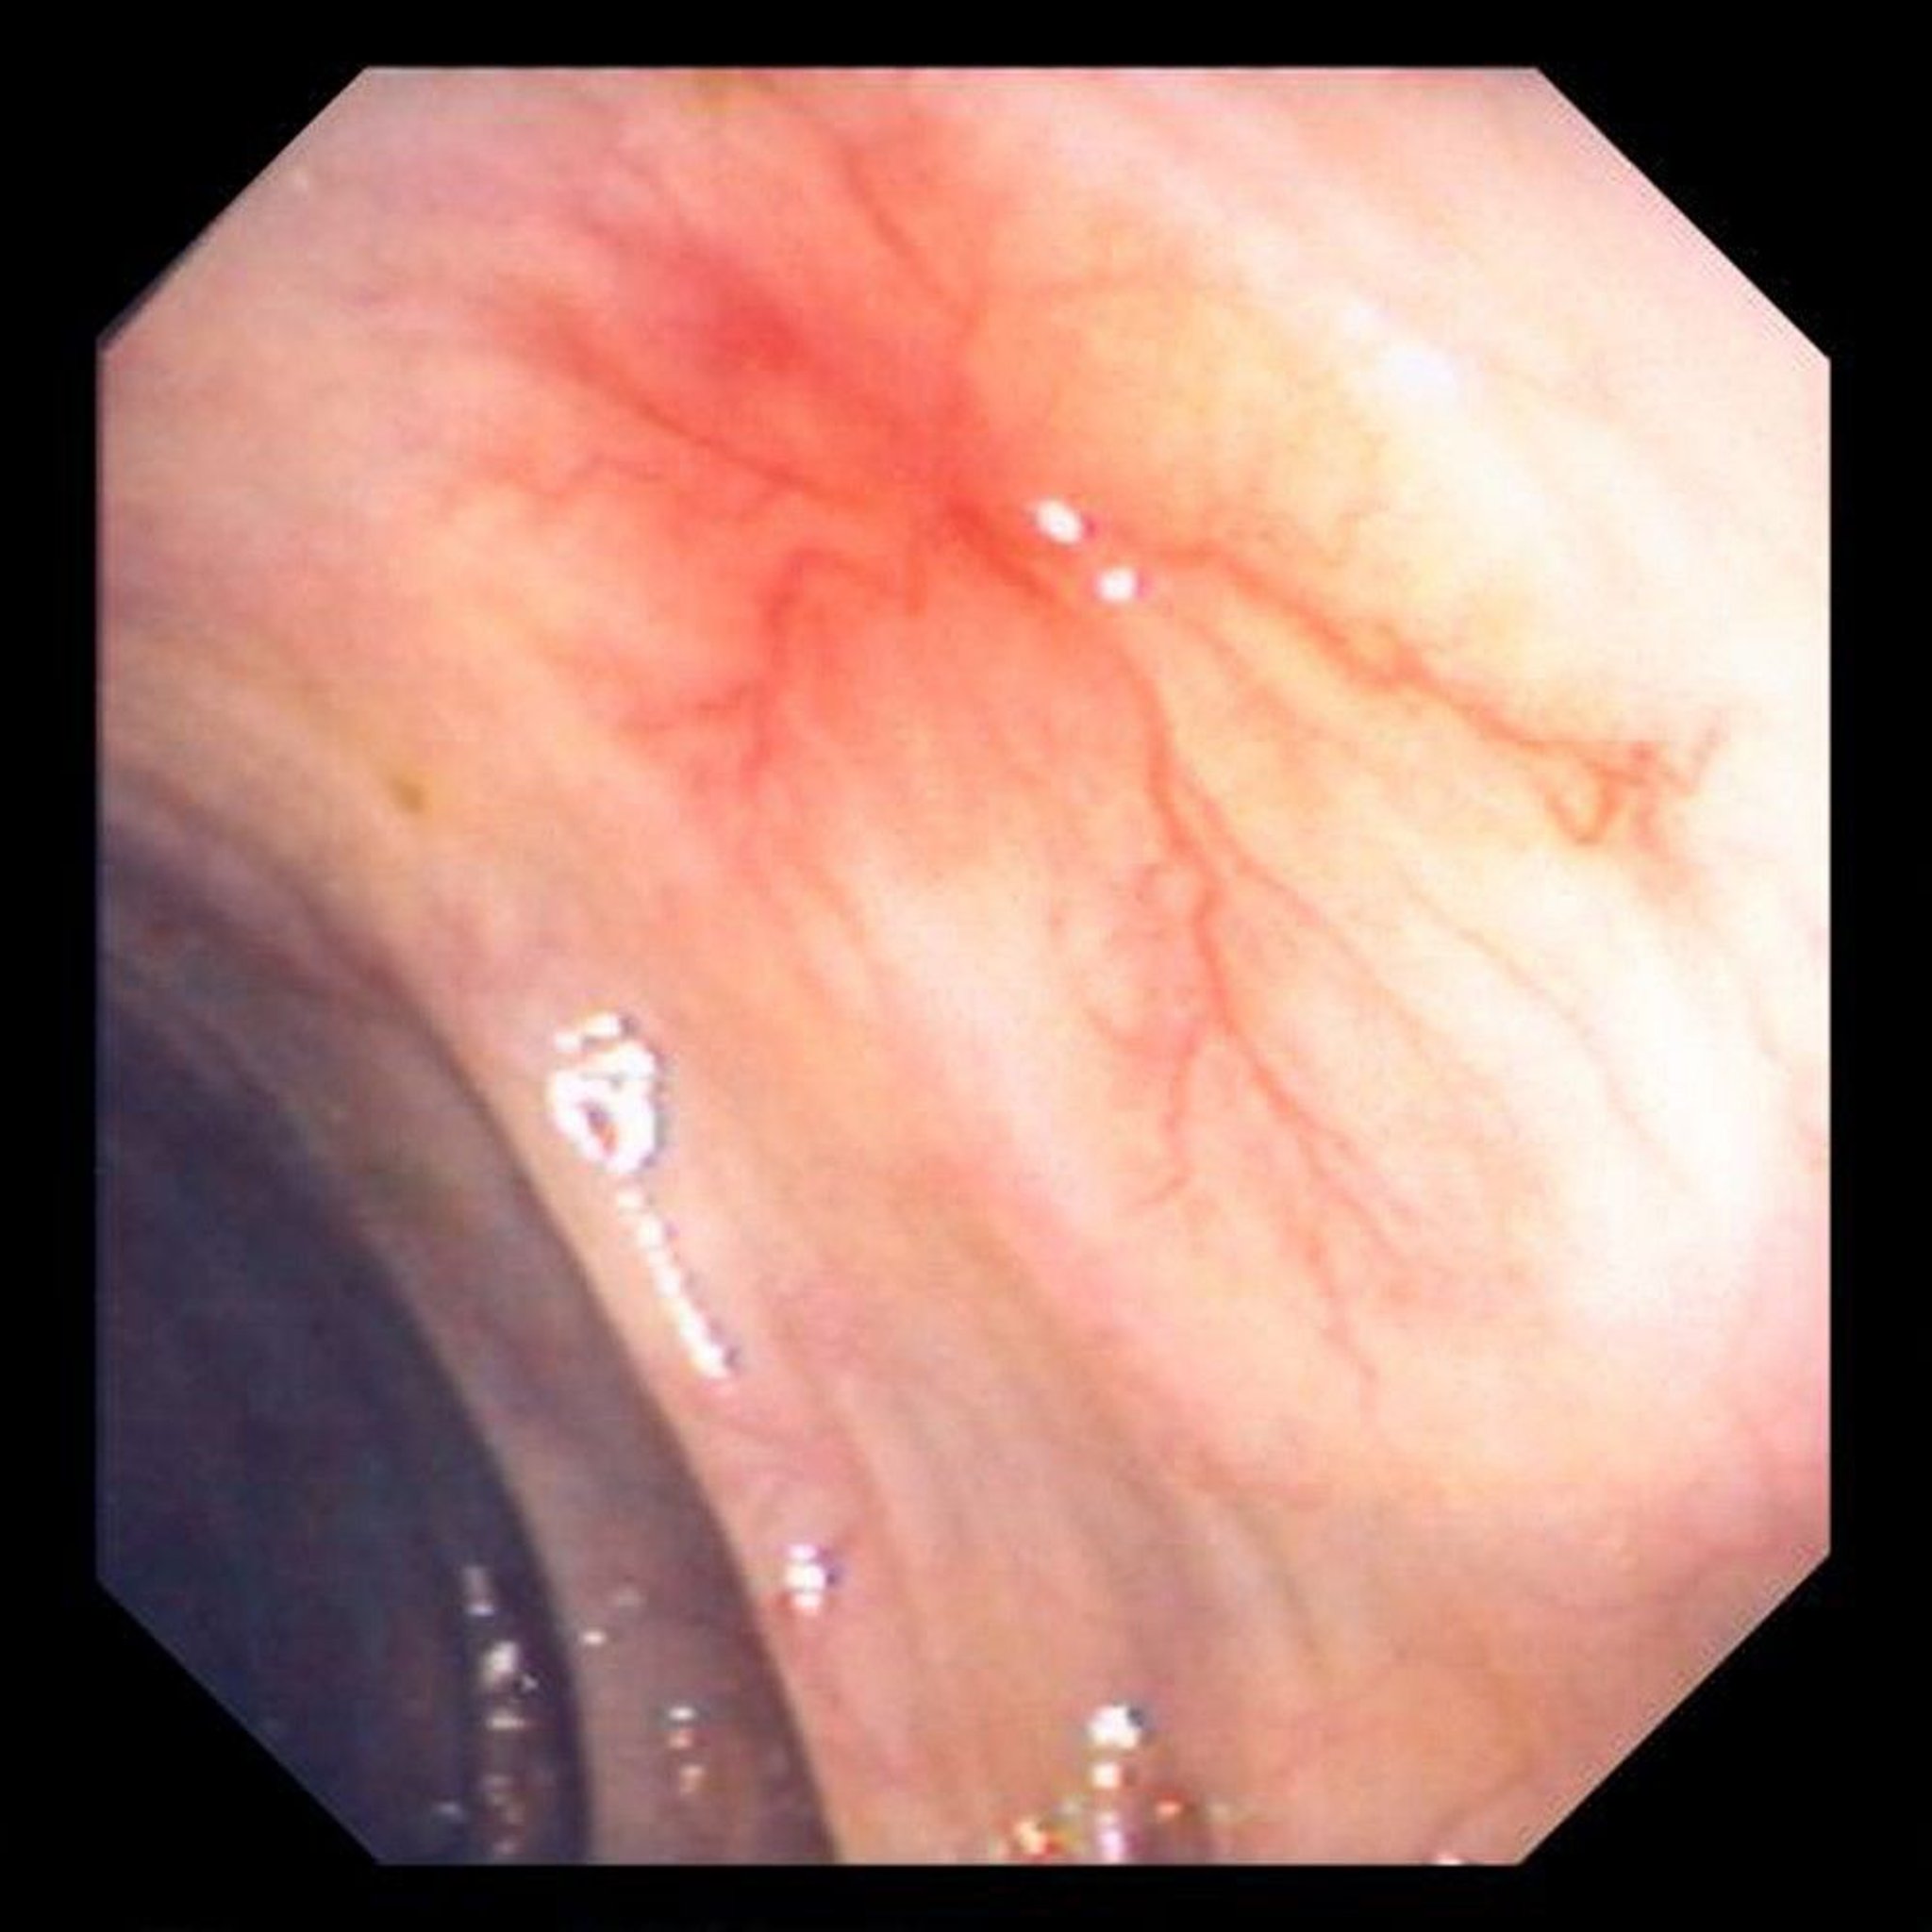

Abnormal Blood Vessels (Angiodysplasia) in the Intestine

This photo shows an abnormal blood vessel in the wall of the bowel.

Image provided by David M. Martin, MD.